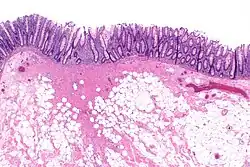

Micrograph showing a colorectal polypectomy scar. H&E stain. | |